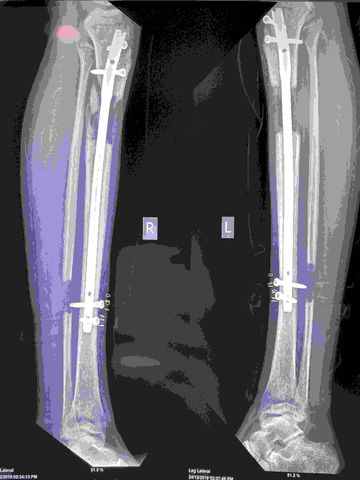

Lengthening Over Nail

Lengthening And Then Nailing

Precice Nail Lengthening

Precice Stryde Nail Lengthening

Cosmetic Limb Lengthening Surgery India

Limb Lengthening Surgery India